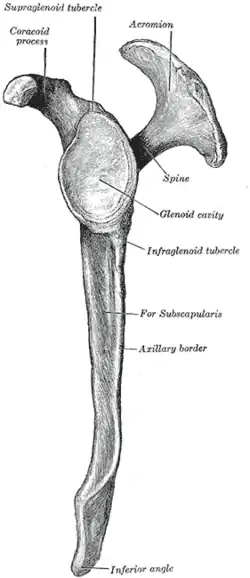

The scapula, on left.

The scapula, on left. Lateral view of the left scapula

Lateral view of the left scapula